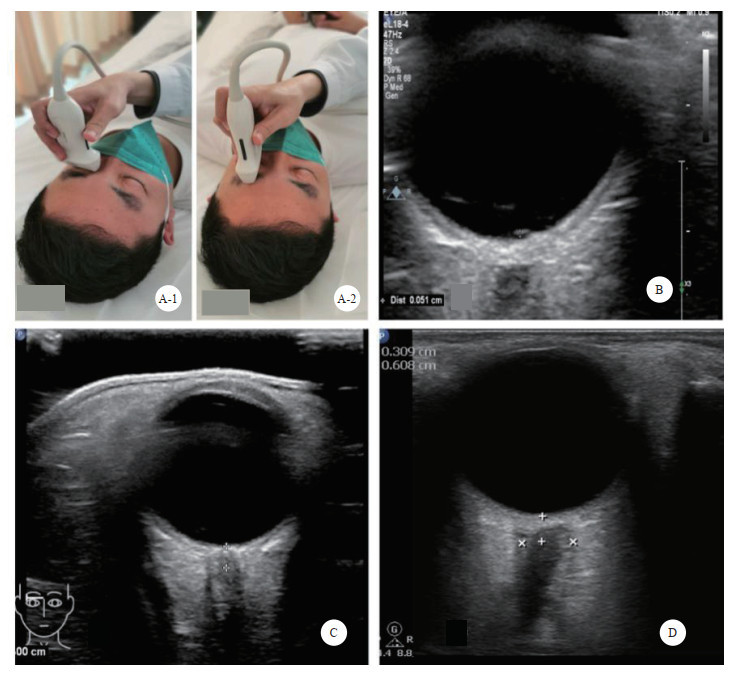

检查方法:采用高频(5.0~10.5 MHz)线阵超声探头。取仰卧位,头保持正中位,双眼睑闭合,眼球尽量固定。探头轻轻地放在闭合的眼睑上,避免过度施压。扫描切面分为横断面和矢状面。调整增益使视神经及其周围组织显示更加清晰。通常选择在眼球后3 mm的位置测量ONSD,测量时与视神经鞘的长轴垂直[27](图 2)。

| A: 视神经鞘探查体位及探头位置,A-1横切, A-2纵切;B:视盘的测量;C:视神经鞘的测量;D:颅高压时,ONSD水肿、增厚 图 2 超声测量视神经鞘直径 |